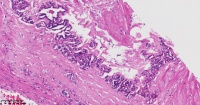

单纯性肾囊肿?

女

年龄

61岁

临床诊断

肾囊肿

一般病史

标本名称

大体所见

符合单纯性肾囊肿,囊壁肾小管内胶样管型沉积